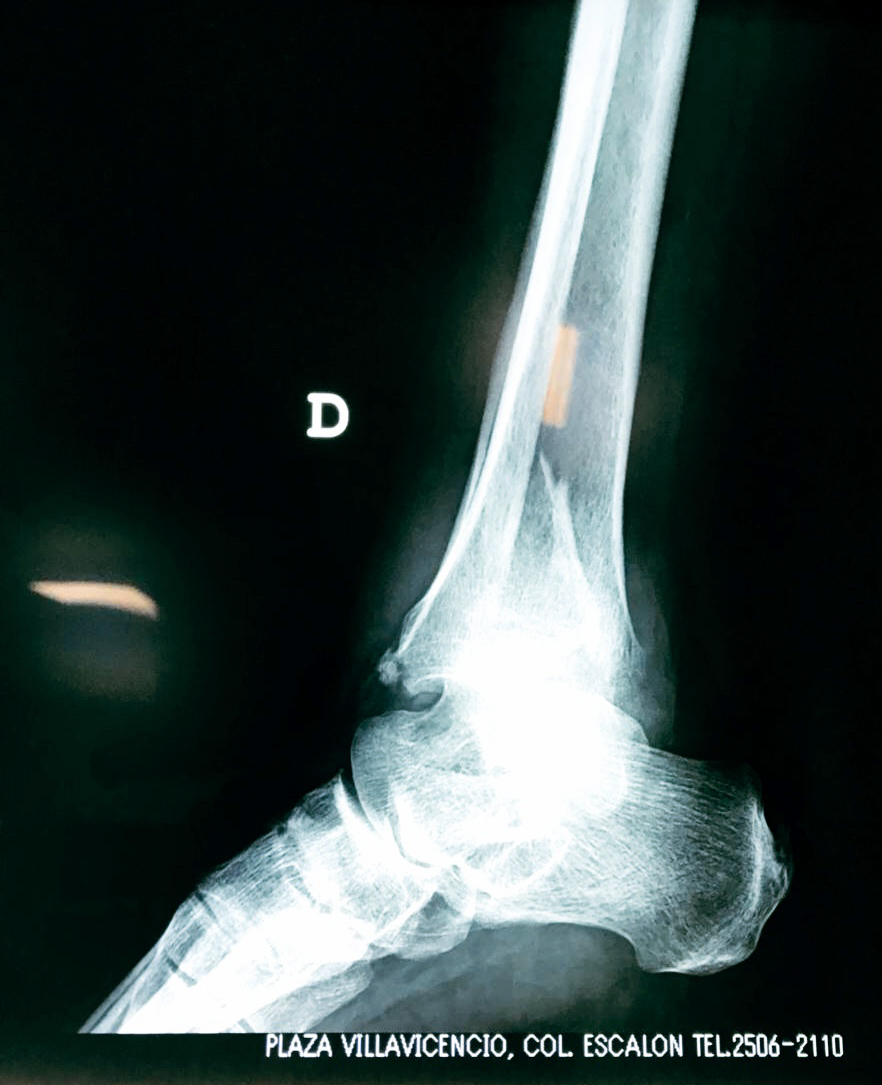

Una fractura de tobillo es la rotura de uno o más de los huesos del tobillo. Estas fracturas pueden ser:

Algunas fracturas de tobillo pueden requerir cirugía si:

- Los extremos de los huesos están desalineados entre sí (desplazados).

Cuando se necesita cirugía, es probable que esta implique el uso de clavijas de metal, tornillos o placas para sostener los huesos en su lugar mientras la fractura se consolida. Los elementos de soporte pueden ser temporales o permanentes.